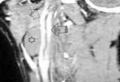

В диагностике боковой кисты шеи большое значение имеет КТ в режиме контрастирования, которая позволяет уточнить локализацию, топографические особенности ее расположения, размеры, плотность содержимого и состояние региональных лимфатических узлов.

На КТ шеи (слева) обозревается наличие инкапсулированной кисты, расположенная кпереди грудино-ключично-сосцевидной мышцы, на уровне подъязычной кости и щитовидного хряща. Форма кисты веретенообразная, размеры 3 см в переднезаднем и 2,5 см в поперечном измерение: вертикальный размер не менее 5 см. Внутри она имеет однородное кистозно-жидкостное содержимое (серозный мукоид) плотностью до 26 ед Н. Сонные артерии и внутренняя яремная вена расположены позади и медиальнее кисты - непосредственно прилегают к ее внутренней поверхности .

На КТ справа по переднебоковой поверхности шеи кпереди от сосудисто-нервного пучка, медиальнее от грудино-ключично-сосцевидной мышцы обозревается плотная тканевая структура которая проецируется на уровне подъязычной кости и щитовидного хряща. Размеры 4х2,5 см. Сонные артерии и внутренняя яремная вена оттеснены медиально.